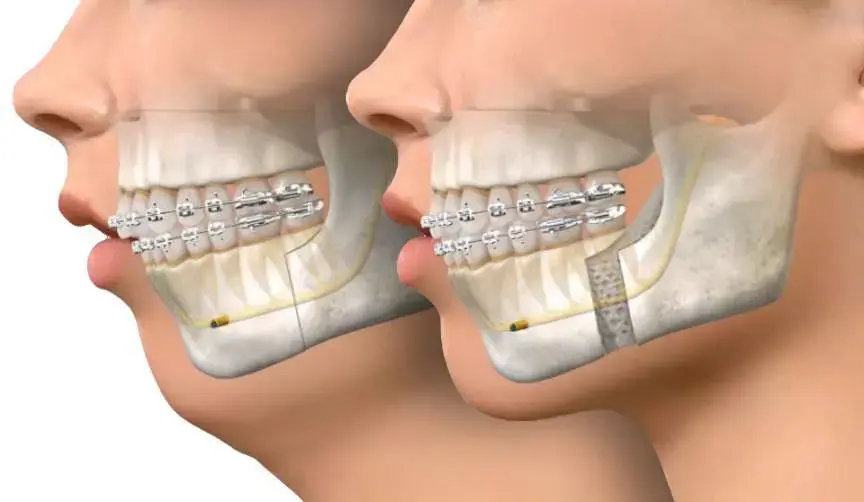

ارتوسرجی یا ارتودنسی همراه با جراحی فک یک روش درمانی است که برای اصلاح مشکلات فکی و دندانی جدی مورد استفاده قرار میگیرد. در این روش، ابتدا ارتودنسی برای تنظیم دندانها و آمادهسازی آنها انجام میشود، سپس جراحی فک برای اصلاح ساختار فک و بهبود عملکرد آن صورت میگیرد. این درمان میتواند مشکلاتی مانند فک جلو، فک عقب، عدم تقارن صورت، بروکسیسم و مشکلات تنفسی را اصلاح کند.

برخی از ناهنجاریهای فکی و دندانی تنها با ارتودنسی قابل اصلاح نیستند و نیاز به ترکیب آن با جراحی فک دارند. این روش که به ارتوسرجری معروف است، برای بیمارانی که مشکلات شدیدی در موقعیت فکها دارند، توصیه میشود. ارتودنسی قبل از جراحی، دندانها را در موقعیت مناسب قرار میدهد و پس از جراحی، تنظیمات نهایی انجام میشود تا فک و دندانها هماهنگ شوند.

۲. ارتودنسی پیش از جراحی: دندانها با براکتهای ثابت مرتب میشوند تا برای جراحی آماده شوند.

3. جراحی فک: جراح فک و صورت موقعیت استخوان فک را اصلاح میکند تا هماهنگی بهتری ایجاد شود.

4. ارتودنسی بعد از جراحی: برای تکمیل درمان و تثبیت نتایج، تنظیمات نهایی دندانها انجام میشود.